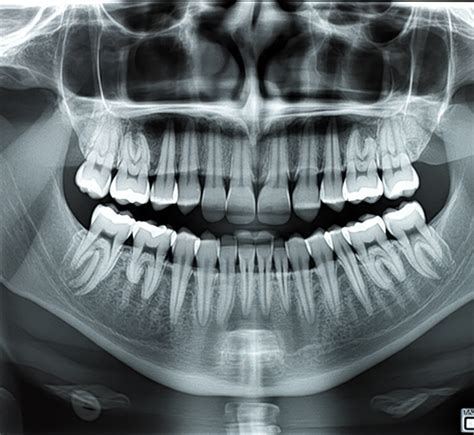

Errores en la Ortopantomografía

La ortopantomografía es una técnica radiológica que proporciona una vista panorámica de los dientes, la mandíbula y el maxilar. Para obtener una imagen de calidad, es crucial evitar ciertos errores:

Un paciente de 58 años fue remitido al Departamento de Prostodoncia para evaluación de un posible tratamiento protésico. Durante la evaluación radiográfica de rutina, se identificó incidentalmente una radiolucidez interradicular asintomática en las regiones 11 y 21. La tomografía volumétrica digital reveló una masa circunscrita interradicular palatina que comunicaba con la fosa nasal izquierda, lo que llevó al diagnóstico de sospecha de un agujero incisivo ensanchado.

El caso presentado destaca la importancia de considerar las variantes anatómicas normales en el diagnóstico radiográfico. El agujero incisivo ensanchado es una variante anatómica normal que carece de significado patológico. En imágenes radiológicas bidimensionales, la sobreproyección de la espina nasal anterior o del tabique nasal puede generar la impresión de una radiolucidez en forma de corazón, lo que sugiere erróneamente un quiste nasopalatino.

Ante la detección de una masa radiotransparente en una radiografía panorámica, se recomienda obtener una segunda radiografía en una proyección distinta. En procesos más extensos, se recomienda recurrir a exámenes radiológicos más detallados, como una tomografía volumétrica digital dental, que proporciona una imagen tridimensional de las estructuras anatómicas.

En pacientes asintomáticos, se debe considerar siempre la posibilidad de que la radiolucidez sea solo la expresión de un agujero incisivo de grandes dimensiones. Los estudios anatómicos han documentado variantes anatómicas normales de hasta 10 mm, con tamaños de 6 a 7 mm no siendo excepcionales.

En el caso presentado, se descartó un proceso patológico, dado que la radiolucidez resultó ser una variante anatómica normal del agujero incisivo. Por ello, se prescindió de tomar alguna medida terapéutica.